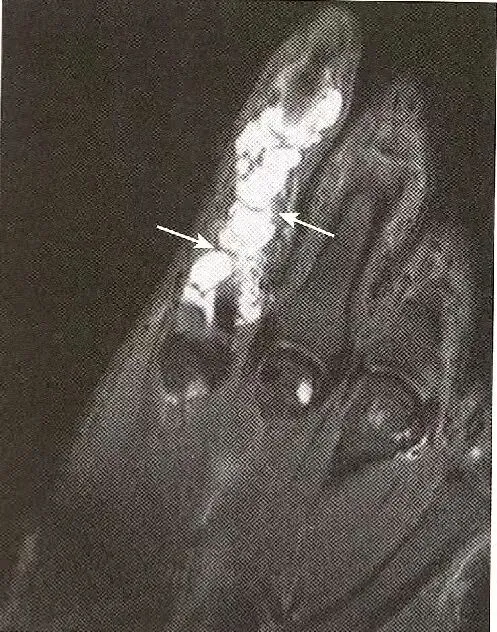

痛风影响肌腱:  肌腱周围分页状的等信号痛风结节